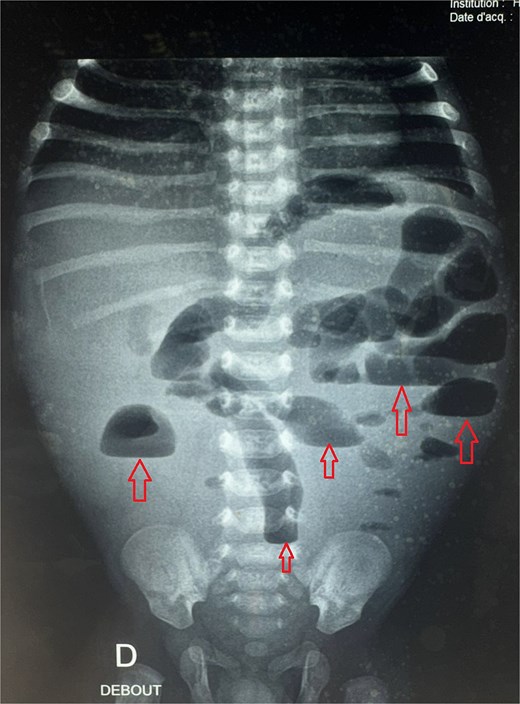

Given the clinical presentation and history of recurrent obstruction, HD was suspected. A contrast enema demonstrated a significant caliber discrepancy between a moderately dilated rectum and a markedly dilated sigmoid colon, suggesting a transition zone. A rectal suction biopsy using Noblett forceps confirmed the absence of ganglion cells in the distal bowel. The patient underwent a Soave endoanal pull-through procedure at 4 months of age (Fig. 3). Histopathological analysis of the resected segment confirmed that the pull-through procedure had been performed in a normally ganglionated area. The postoperative recovery was uneventful. The child is currently 3 years old, with normal bowel function and no need for laxatives or enemas. There are no associated congenital anomalies, and the genetic evaluation revealed no abnormalities.

Intraoperative view of a transanal endorectal pull-through (soave procedure) for HD.